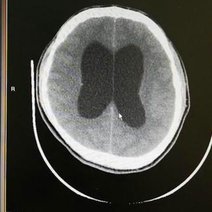

脑动脉瘤是颅内动脉血管的异常瘤状突起。脑动脉瘤不破裂,一般病人没有明显症状,如果破裂出血,常表现为蛛网膜下腔出血,病人可以出现剧烈的头痛,恶心呕吐,甚至出现...11216人收听

- 数字减影血管造影技术,颅内动脉瘤介入治疗,湘雅护理学院,颅内动脉瘤,颅内动脉瘤系指脑动脉壁的异常膨出部分,是引起自发性蛛网膜下腔出血的最常见原因。病因-尚不甚清楚,但以先天性动脉瘤占大部分。任何年龄可

- 动瘤DavidSLiebeskind1引1.1景动瘤是有破倾向的管结构的病理性局灶性扩张。些管异常常根据假定的病因分类。囊状、浆果状或先天性动瘤占全动瘤的90

- 脑动脉瘤相关知识脑动脉瘤简单说就是脑动脉血管壁上膨出的血管泡,血管泡在血液不间断的冲击下,就象吹气球一样,球吹得越大,血管壁就变得越薄,血管也就越容易破裂。一般认为